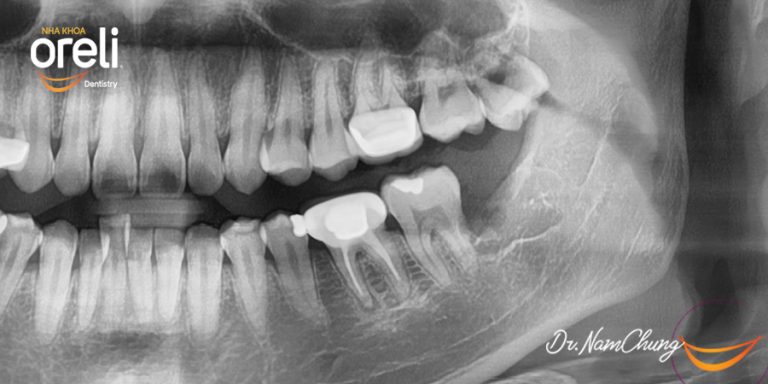

Nhổ răng khôn hàm dưới khó – Kết quả sau điều trị tại Oreli

Nhổ răng khôn

Mọc lệch

Xem thêm